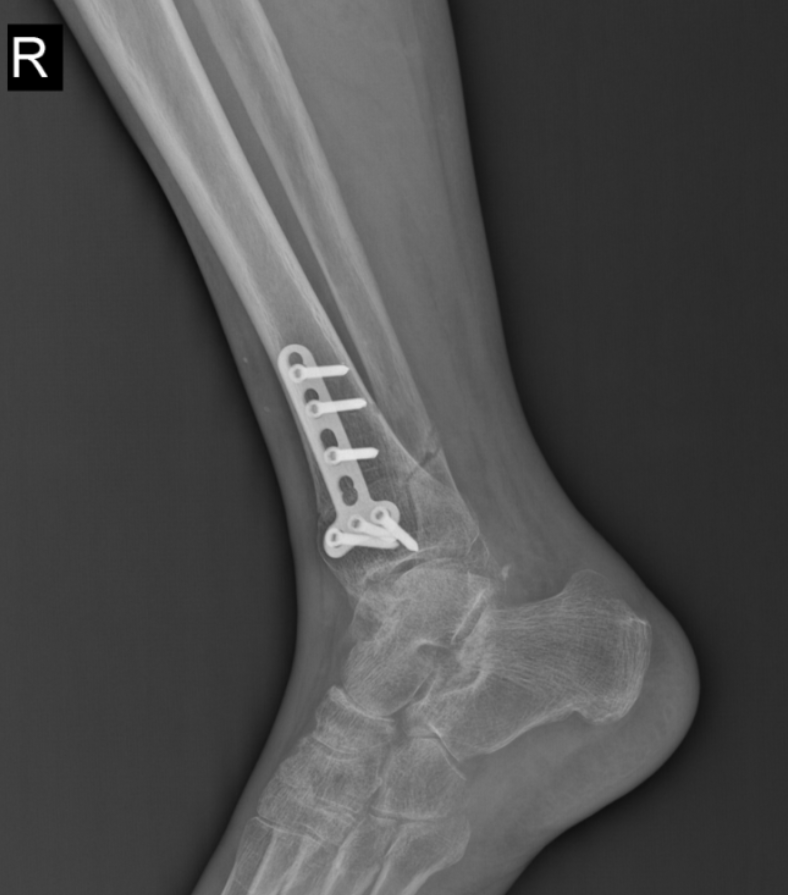

踝上截骨治疗踝关节关节病及距骨骨软骨损伤的手术治疗,对医生手术技术要求高,需要对踝足部的力线及平衡调整有丰富临床经验,术中要有很强应变能力。在李恒和足踝外科小组配合下顺利完成!

术后复查X线,非常完美。李恒提醒,踝关节是人体中负重最大的关节,出现问题会给生活带来极大的痛苦和不便,崴脚并非小事,若早期处理不当,错过最佳治疗时机,轻则遗留慢性疼痛,重则导致创伤性关节炎、慢性踝关节不稳等后遗症,所以“走路看路”+“积极的运动锻炼”,预防踝关节损伤非常重要!